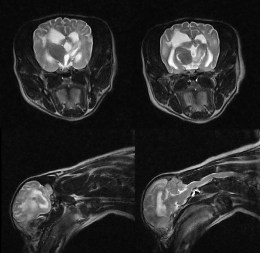

Високодеталізоване МРТ зображення нейрокраніуму собаки в поперечній проекції з чіткою візуалізацією структур мозку

Покращена візуалізація патологій

Система забезпечує високу діагностичну ефективність при виявленні дегенеративних змін міжхребцевих дисків, пухлинних процесів та запальних захворювань центральної нервової системи